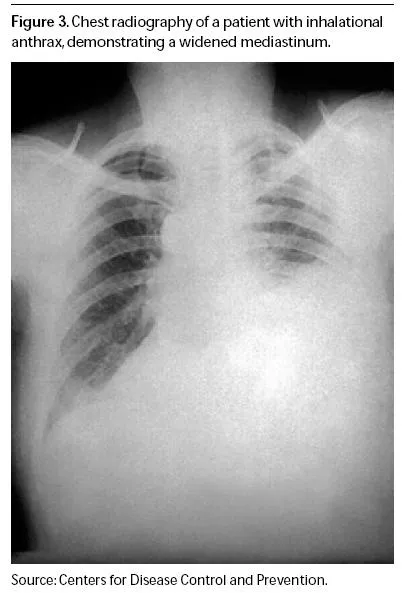

⭐ A widened mediastinum on chest X-ray is a classic finding in inhalational anthrax.

- Cutaneous anthrax presents with a painless black eschar; pulmonary anthrax shows a widened mediastinum on chest X-ray.